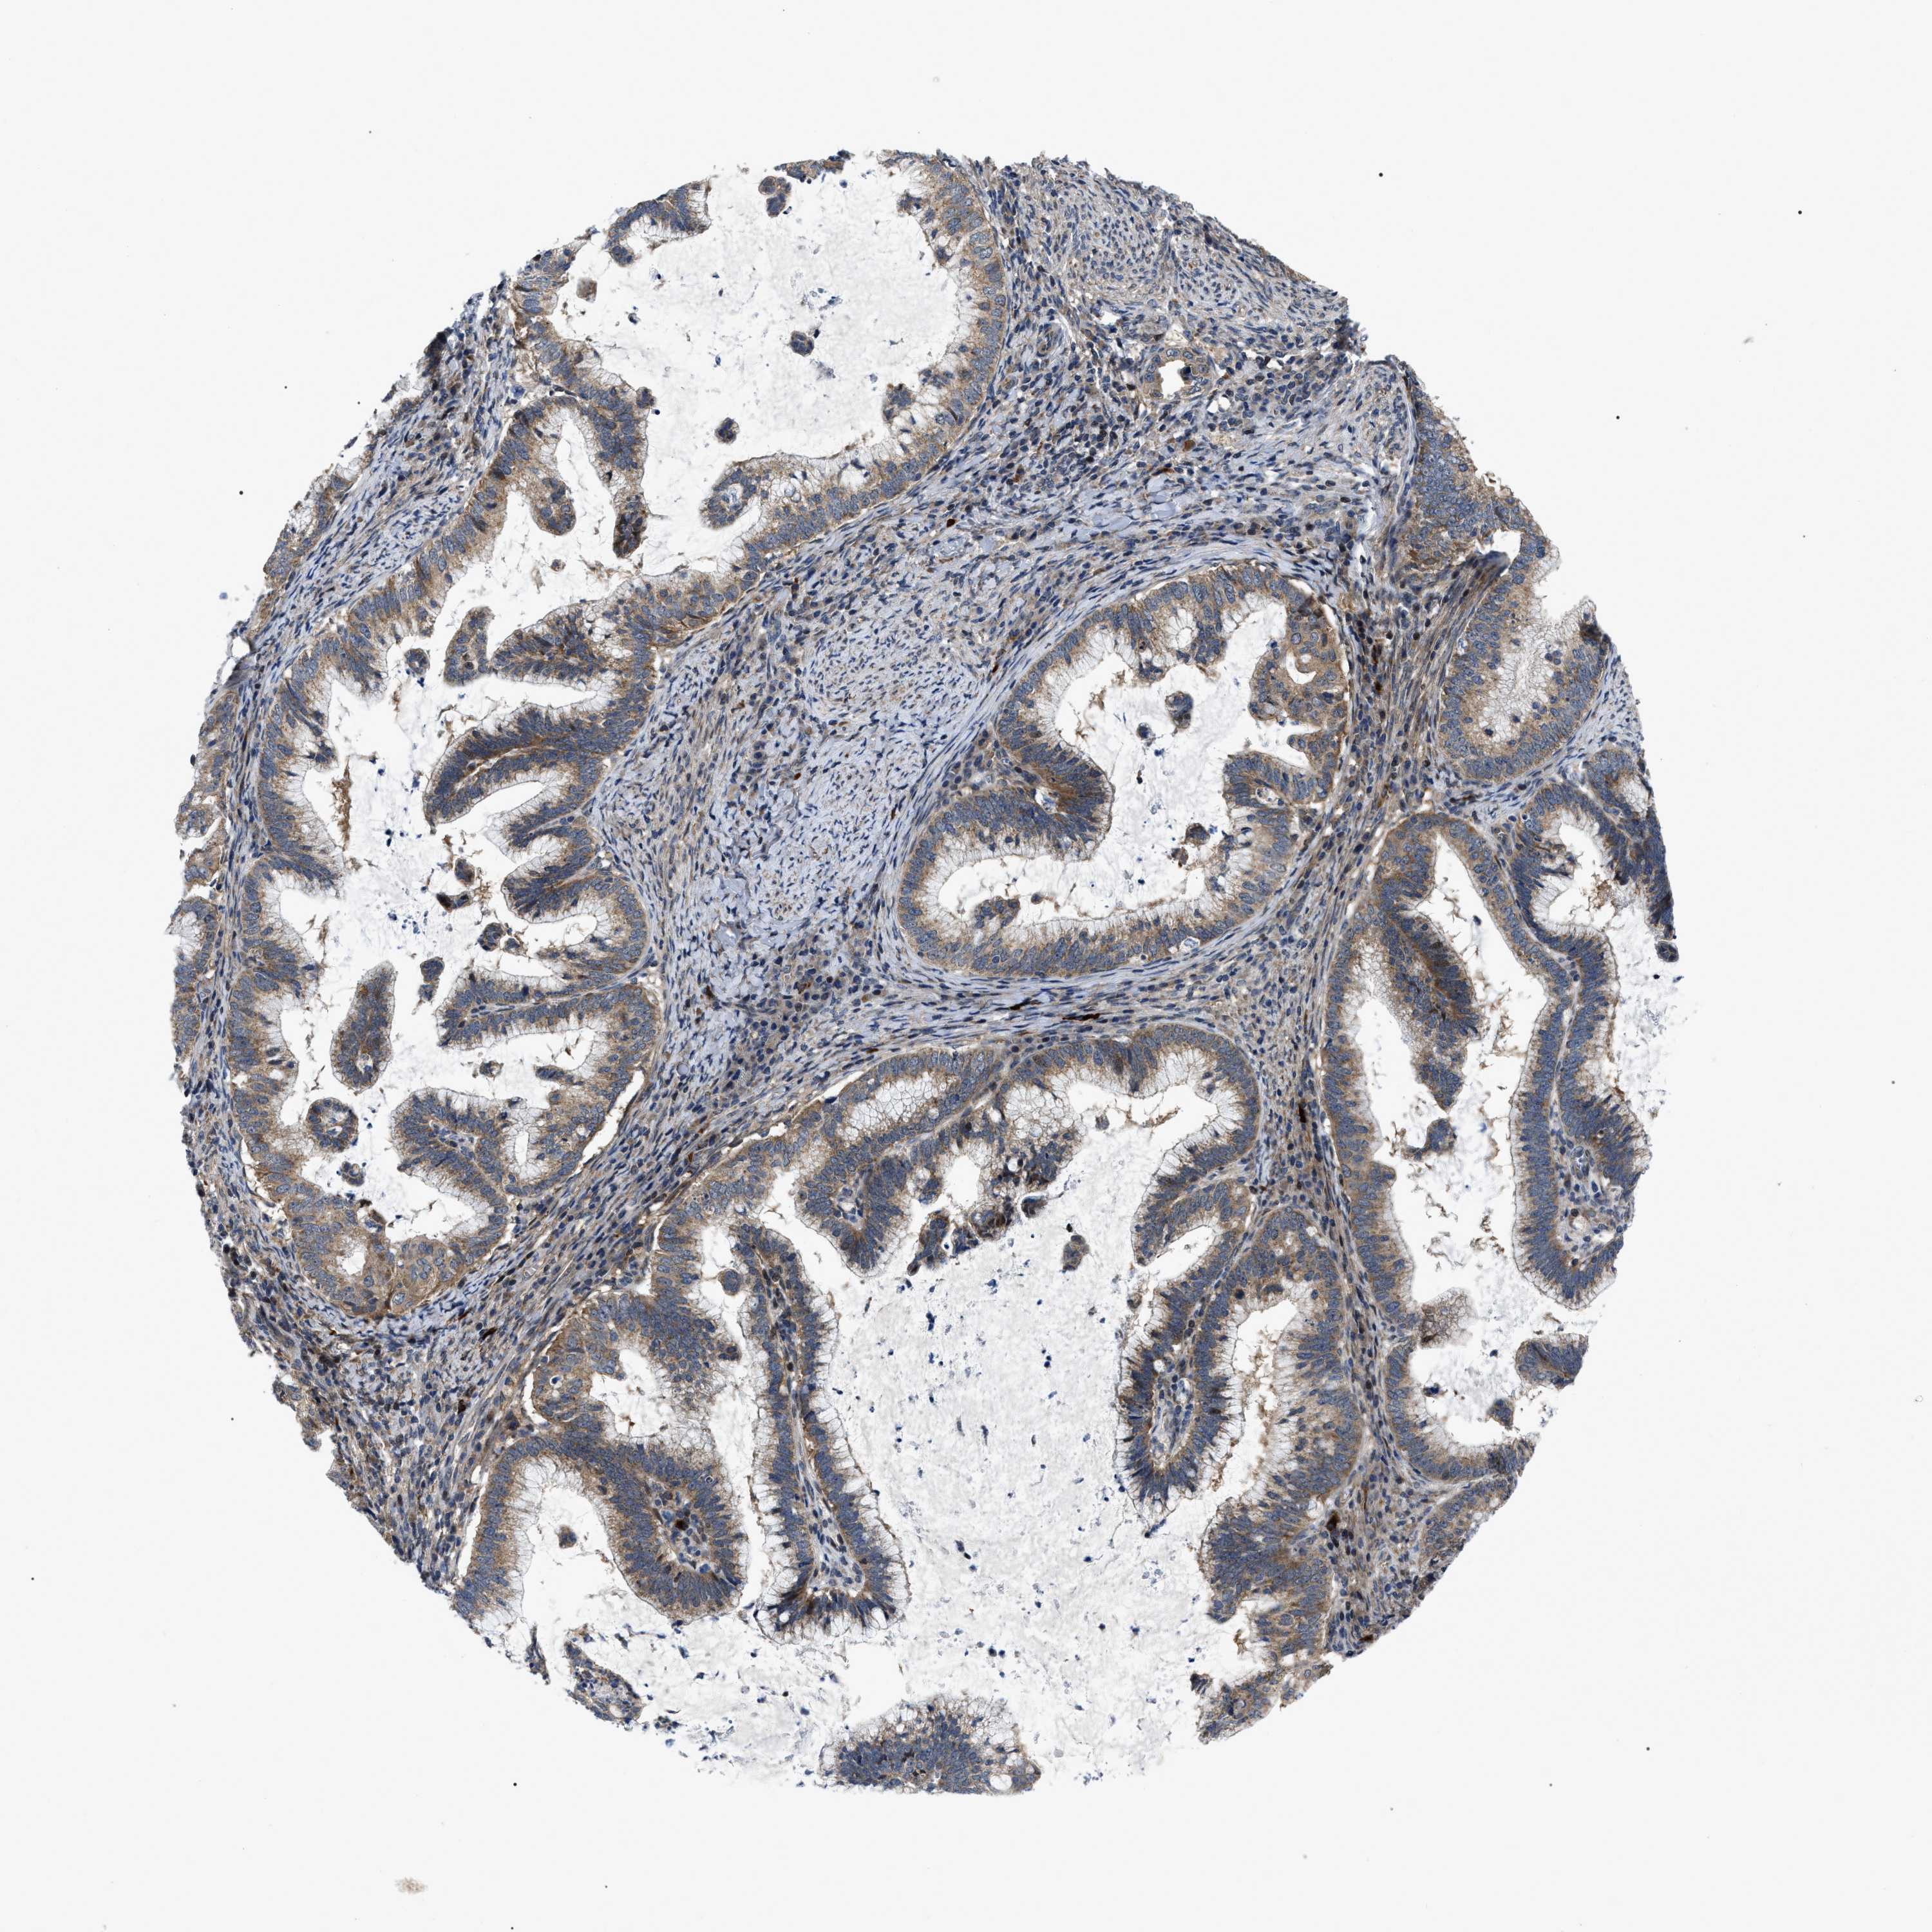

CERVICAL CANCER - Protein expressioni

A mouse-over function shows sample information and annotation data. Click on an image to view it in a full screen mode. Samples can be filtered based on level of antibody staining by selecting one or several of the following categories: high, medium, low and not detected. The assay and annotation is described here.

Note that samples used for immunohistochemistry by the Human Protein Atlas do not correspond to samples in the TCGA dataset.

Antibody stainingi

Antibody staining in the annotated cell types in the current human tissue is reported as not detected, low, medium, or high, based on conventional immunohistochemistry profiling in selected tissues. This score is based on the combination of the staining intensity and fraction of stained cells.

Each image is clickable and will lead to virtual microscopy that enables deeper exploration of all samples and also displays staining intensity scores, fraction scores and subcellular localization as well as patient and tissue information for each sample.

Antibody HPA019353

Antibody HPA019360

Staining

High

Medium

Low

Not detected

Intensity

Strong

Moderate

Weak

Negative

Quantity

>75%

75%-25%

<25%

None

Location

Nuclear

Cytoplasmic/membranous

Cytoplasmic/membranous,nuclear

Squamous cell carcinoma, NOS

Adenocarcinoma, NOS